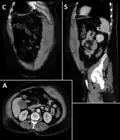

Rectus sheath hematoma seen on axial CT – with active bleeding under Marcoumar -